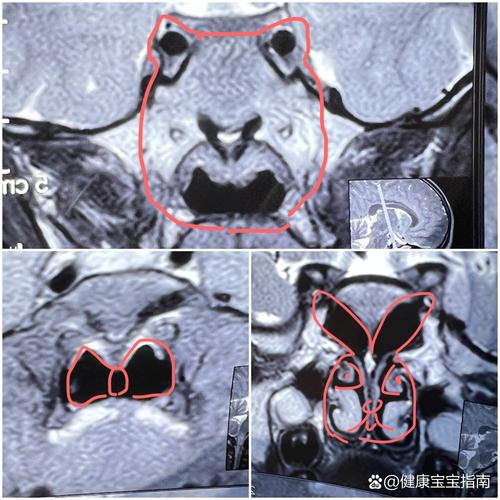

MRI能提供非常清晰、精细的身体内部结构图像,对于儿童来说,它是诊断以下疾病的重要工具:

- 神经系统问题:这是儿童MRI最常见的应用。

- 脑部:脑发育异常、脑炎、脑肿瘤、癫痫病因查找、脑损伤(如缺氧后)、智力发育迟缓等。

- 脊髓:脊柱畸形、脊髓肿瘤、脊髓炎等。

- 心脏和血管问题:儿童心脏MRI可以清晰显示心脏结构和功能,是评估先天性心脏病的重要手段。